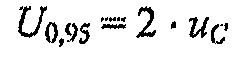

6.6. Вычисляют расширенную неопределенность, %, для доверительной вероятности Р = 0,95 по формуле:

(10)

6.7. Рассчитывают абсолютную расширенную неопределенность по формуле:

,

,

(11)

6.8. Результаты измерений заносят в протокол измерений в виде:

,

,